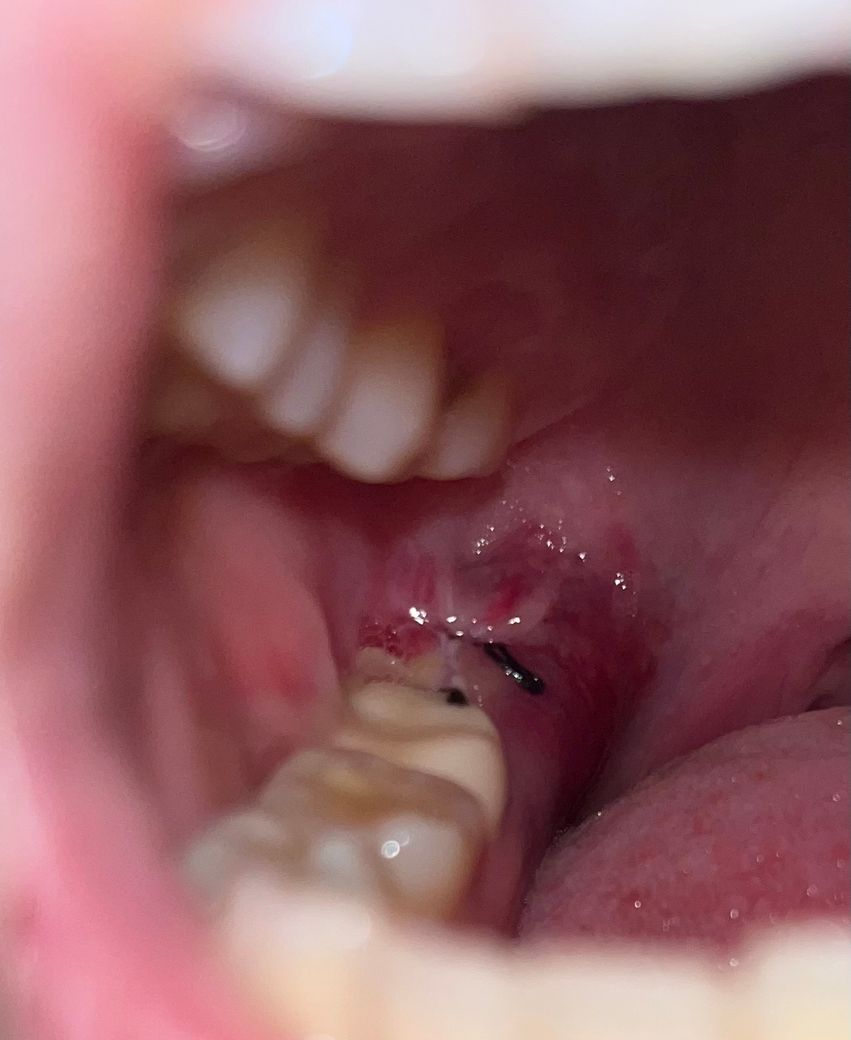

사랑니 발치 잘 아물고 있는건가요??

발치 3일차인데 실밥이 좀 풀리고 통증도 아직 있어요 사진상으로 봤을때 주변이 붉은색인데

잘 아물고 있는 거 맞나요???????

• 1번 째 사진

특별히 문제가 되는 부분이 보이지 않습니다. 아직까지 일주일이 지나지 않았음으로 부분적으로 통증 및 불편감은 나타날 수 있습니다. 갑자기 심하게 나타나는 통증이 아니라면 일주일 정도는 소염진통제 등을 복용하면서 해당 부위를 관찰해볼 필요가 있습니다.

현재 사진상 잘 아물고 있는 것으로 보이며, 만약 통증이나 붓기가 심해지는 경우에는 치과 진료가 필요로 됩니다. 그렇지 않는 경우에는 염증이 덧나지 않도록 소독용 헥사메딘 가글액으로 가글하여 관리하길 권합니다.

사진으로 봤을 경우 잘 아물고 있는 것으로 보입니다.

주변의 발적은 있을 수 있는 증상이며 사진상 염증같은 이상은 없어보입니다. 괜찮은 것 같습니다.

사진상으로 보면 크게 문제가 잇어 보이진 않습니다. 잘 아물고 있으니 너무 걱정하지 않으셔도 될것같습니다.